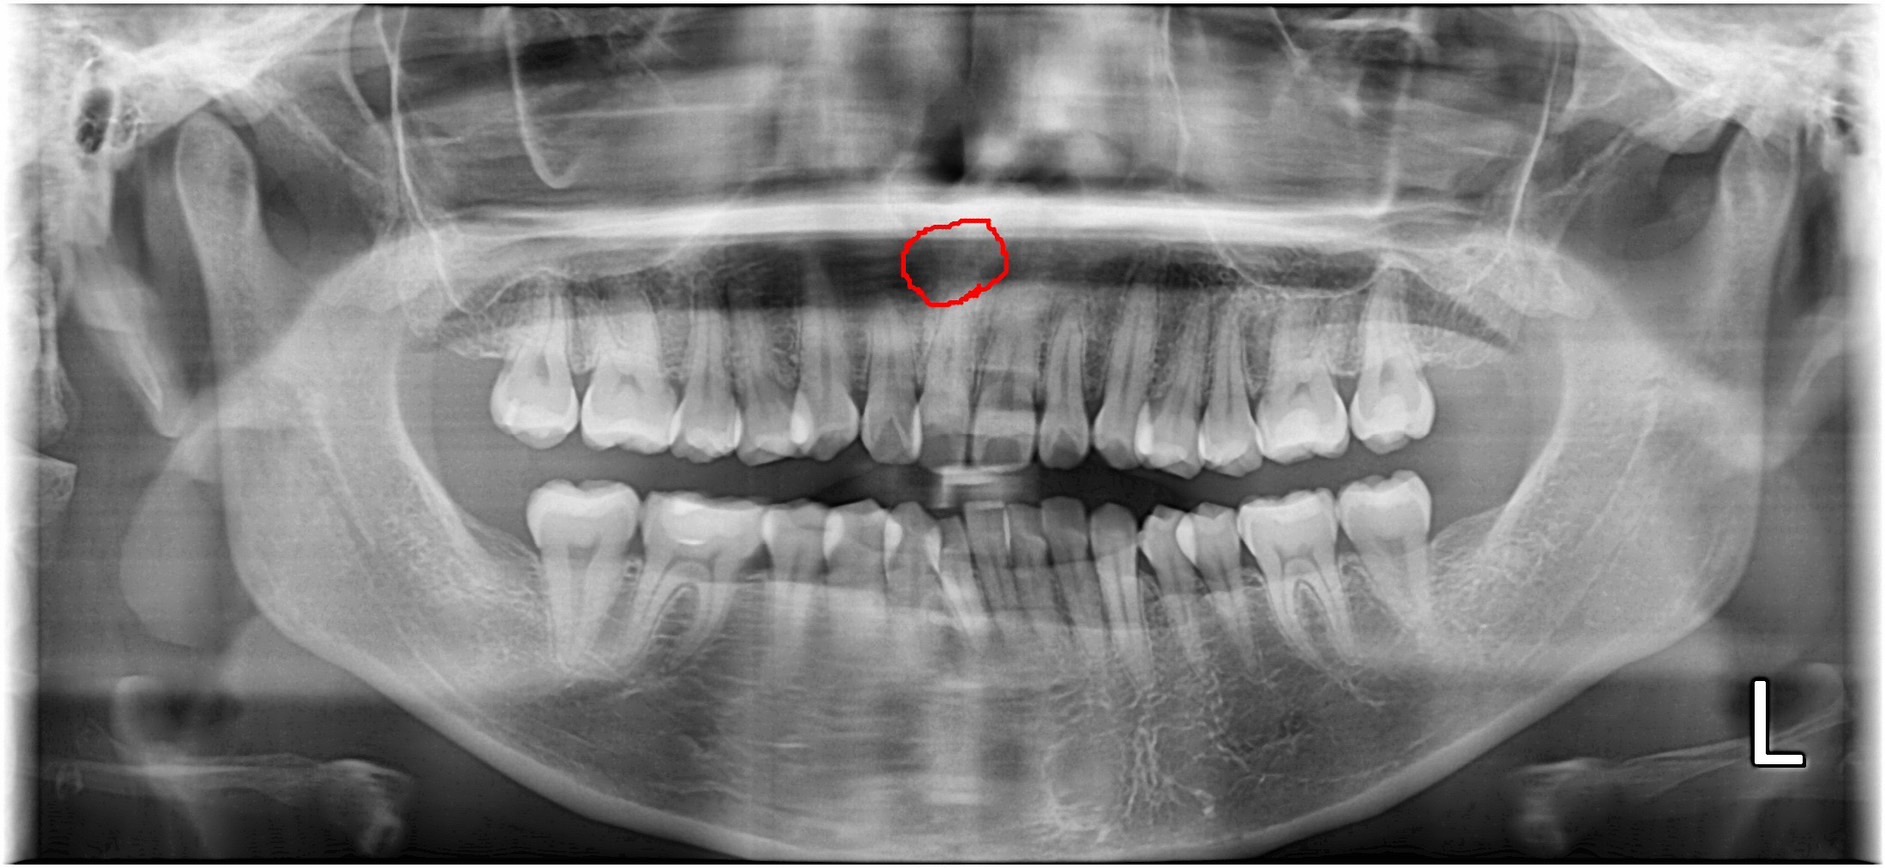

なので下の親知らずはしっかり写真を撮ってどうやって生えているのかを見て慎重に抜きます。